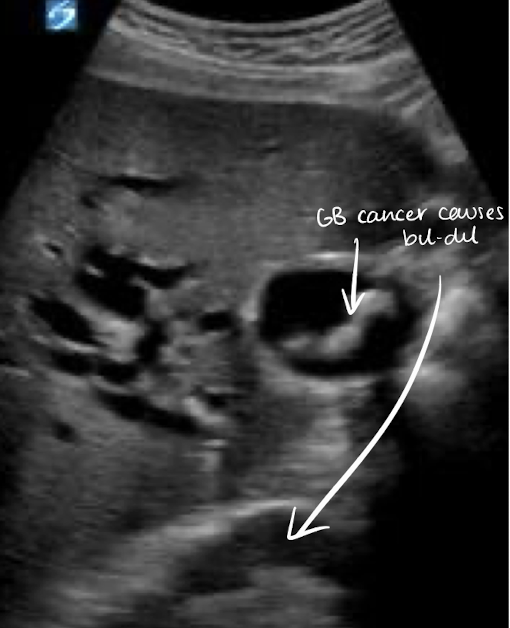

SONO: gallbladder carcinoma

heterogeneous or semi-solid soft tissue mass centered in the GB

thickened and irregular wall

adjacent liver heterogeneous due to invasion

dilated biliary ducts (“bil-dil”)

??

gallbladder carcinoma

GB mass —> “bil-dil”